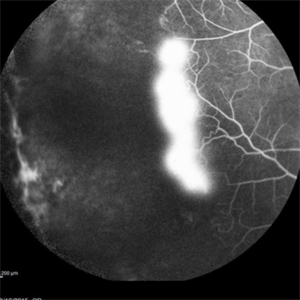

Angiography showed normal vessels posteriorly but severe capillary drop out throughout the periphery OU with scattered severe neovascularization at the edge of the capillary drop out peripherally.

Sickle Cell Retinopathy Sickle Cell RetinopathySep 13 2015 by Thomas A. Ciulla, MD, MBA, FASRS Angiography showed normal vessels posteriorly but severe capillary drop out throughout the periphery OU with scattered severe neovascularization at the edge of the capillary drop out peripherally. Photographer: Thomas Steele Condition/keywords: peripheral retinal neovascularization, sea fan, sickle cell retinopathy